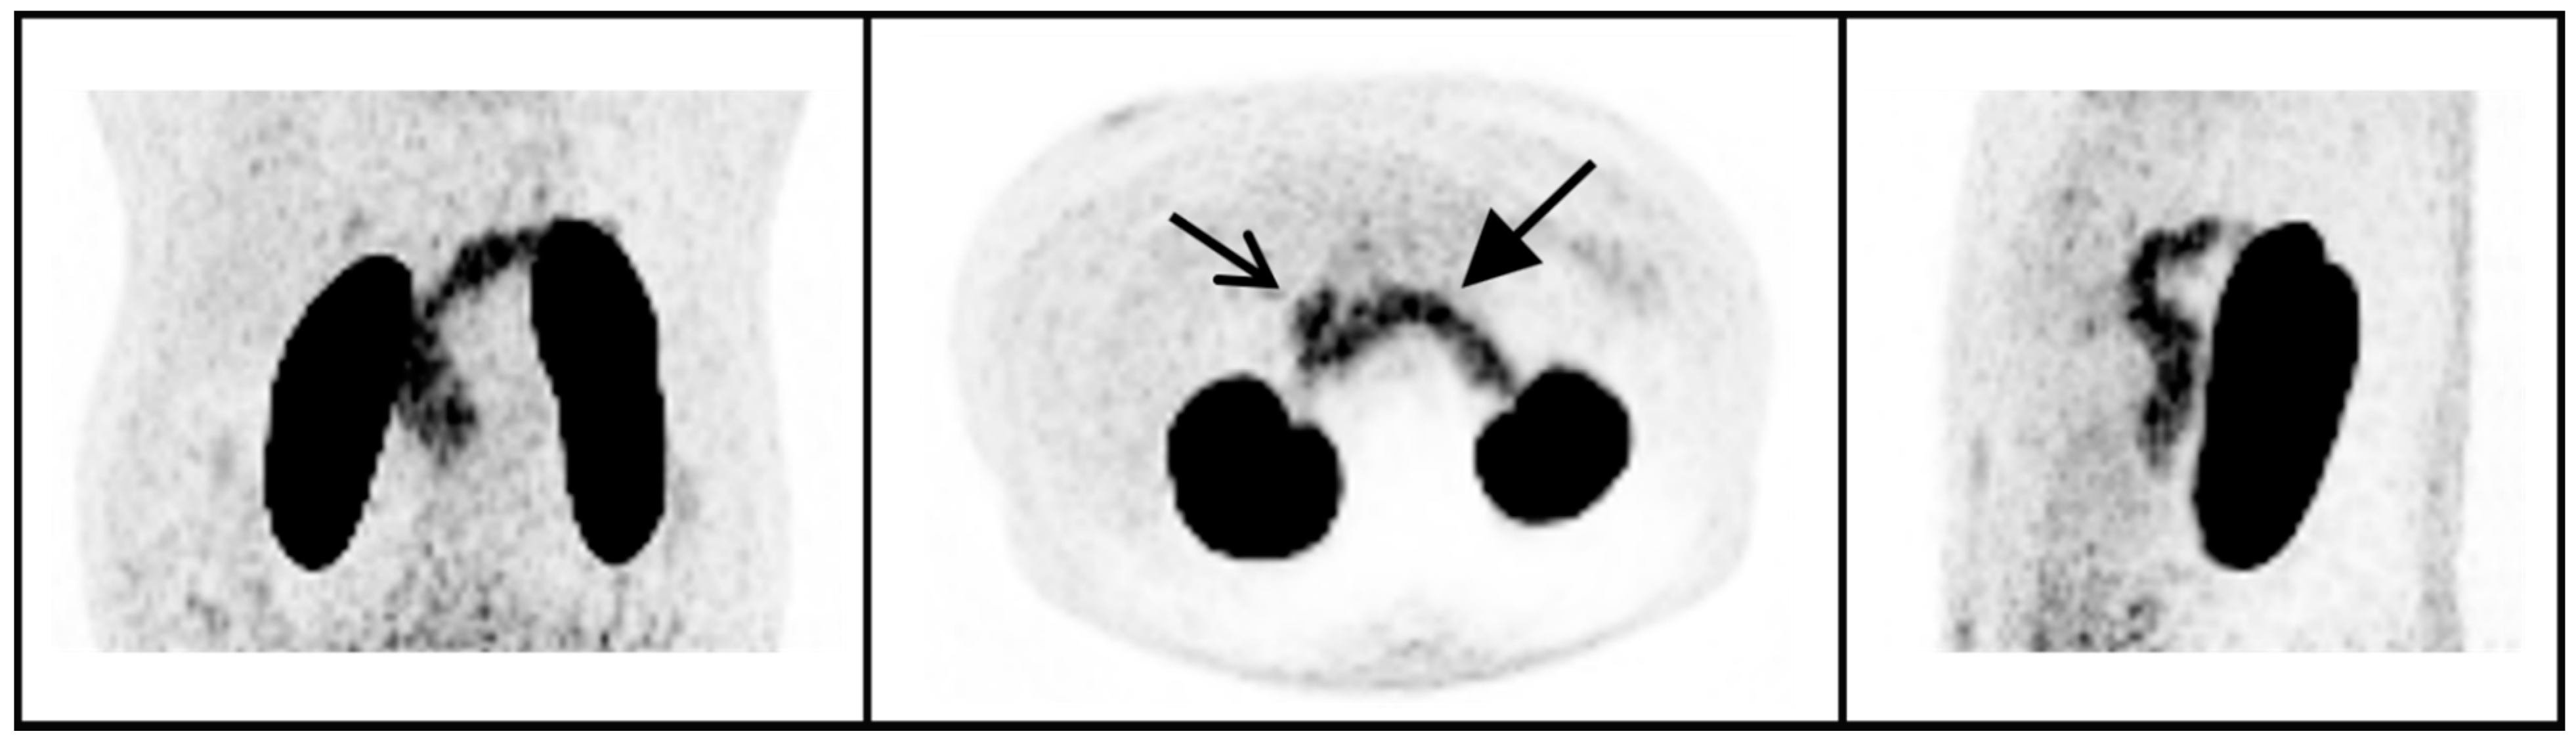

In peripheral organs, clear uptake of 68Ga-NODAGA-exendin-4 was visible in the pancreas (Figure 2), with an average SUVmean of 5.5 ± 1.8 (range 2.3–8.1) and SUVmax of 10.3 ± 3.0 (range: 5.0–15.5). In the blood pool, average SUVmean was 1.5 ± 0.23 and in background tissues highest uptake levels were measured in the liver (SUVmean: 0.67 ± 0.17) and lowest in subcutaneous adipose tissue (SUVmean: 0.20 ± 0.054).

In this study, we show that there is no significant uptake of 68Ga-NODAGA-exendin-4 in the brain (parts inside the blood–brain barrier; BBB) of subjects with obesity, although there is clear uptake in the pituitary. We also reproduce the accumulation of 68Ga-NODAGA-exendin-4 PET in the pancreas [31].

Figure 2. 68Ga-NODAGA-exendin-4 PET maximum intensity projections of the abdomen of one subject in a coronal, axial, and sagittal view (left, middle, and right panel, respectively). Uptake in the pancreas (closed arrow), duodenum (open arrow) and kidneys can be observed.